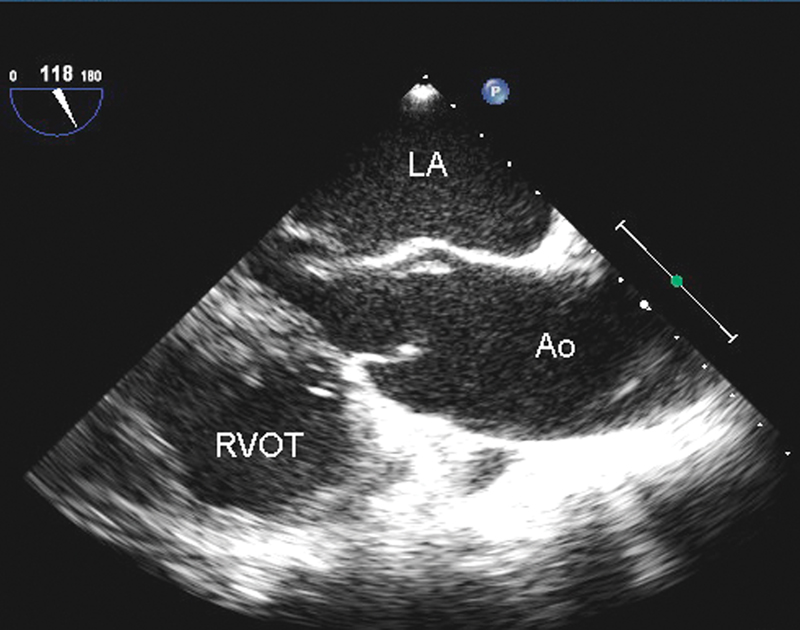

فحوصات تشخيصية لبعض امراض القلب والشرايين التاجية